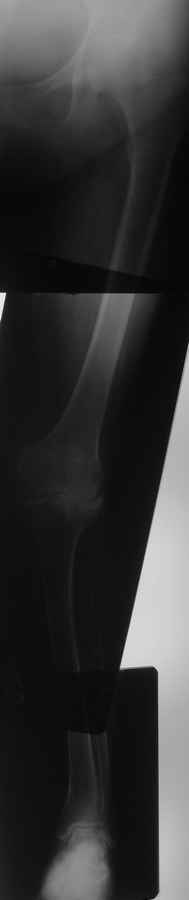

Уважаемые коллеги, интересует мнение специалистов по следующему случаю. Пациентка 56 лет, поступила в отделение для эндопротезирования коленного сустава. Уважаемые коллеги, интересует мнение специалистов по следующему случаю. Пациентка 56 лет, поступила в отделение для эндопротезирования коленного сустава.9 лет больна ревматоидным артритом.Во вложении осевой снимок конечности, после анализа которого в отделении возникла дискуссия.Как поступить-сразу пойти на TKR или сначала выполнить коррекцию оси голени? Если предпочесть эндопротезирование, то каких трудностей ожидать и какой системой воспользоваться(Скорпио или LCS)? А может выполнить протезирование под контролем навигации? Будут интересны любые мнения и замечания. Заранее спасибо всем откликнувшимся.

Уважаемый Салават, а как Вы расцениваете состояние ТБС? Нет ли там проблем? Если это не артефакт, то по законам ортопедии начинать надо сверху....

Прошу прощения за качество снимков.Ни рентгенологически,ни клинически тазобедренные суставы не внушают опасений.Пациентку они не беспокоят.

э-протез - Скорпио(вкладыш-12.5), артротомия-наружняя, с отсечением бугристости.Получилось, по нашему мнению, неплохо. Хотелось бы услышать мнения и замечания участников Ортофорума - во вложении фото на этапах операции и осевой снимок.Еще раз всем спасибо.